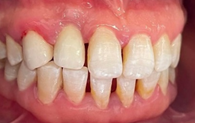

Intraoral examination showed an inadequate hygiene, a Periodontal thick ,a sufficient attached gingiva , a defective mesially extended metal-resin bridge replacing the 12 and a symmetry of the neck line. (Figures 2–4)

Figure 4 OIM.